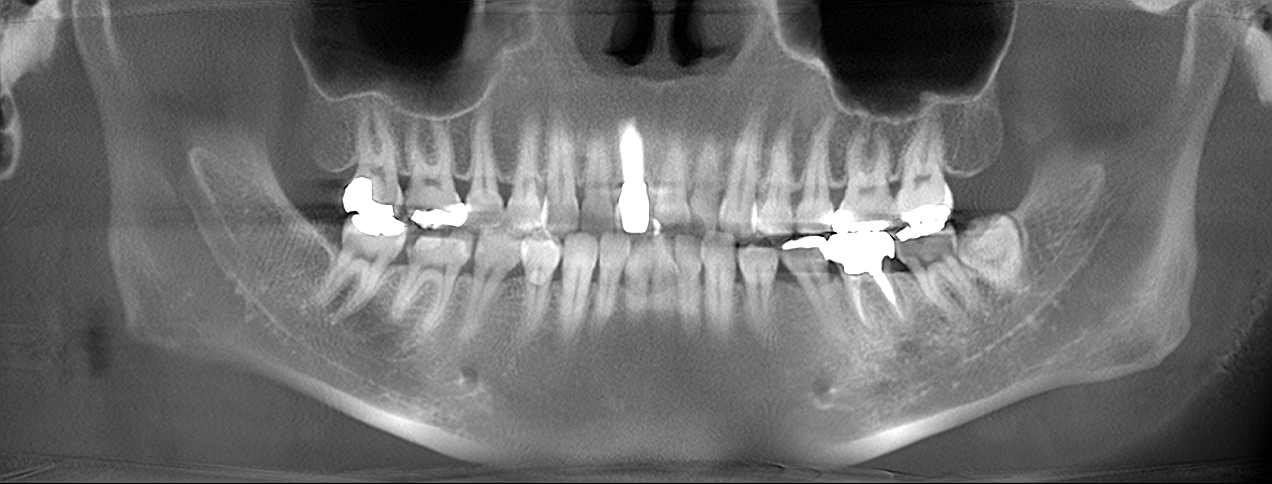

埋入後のパノラマになります